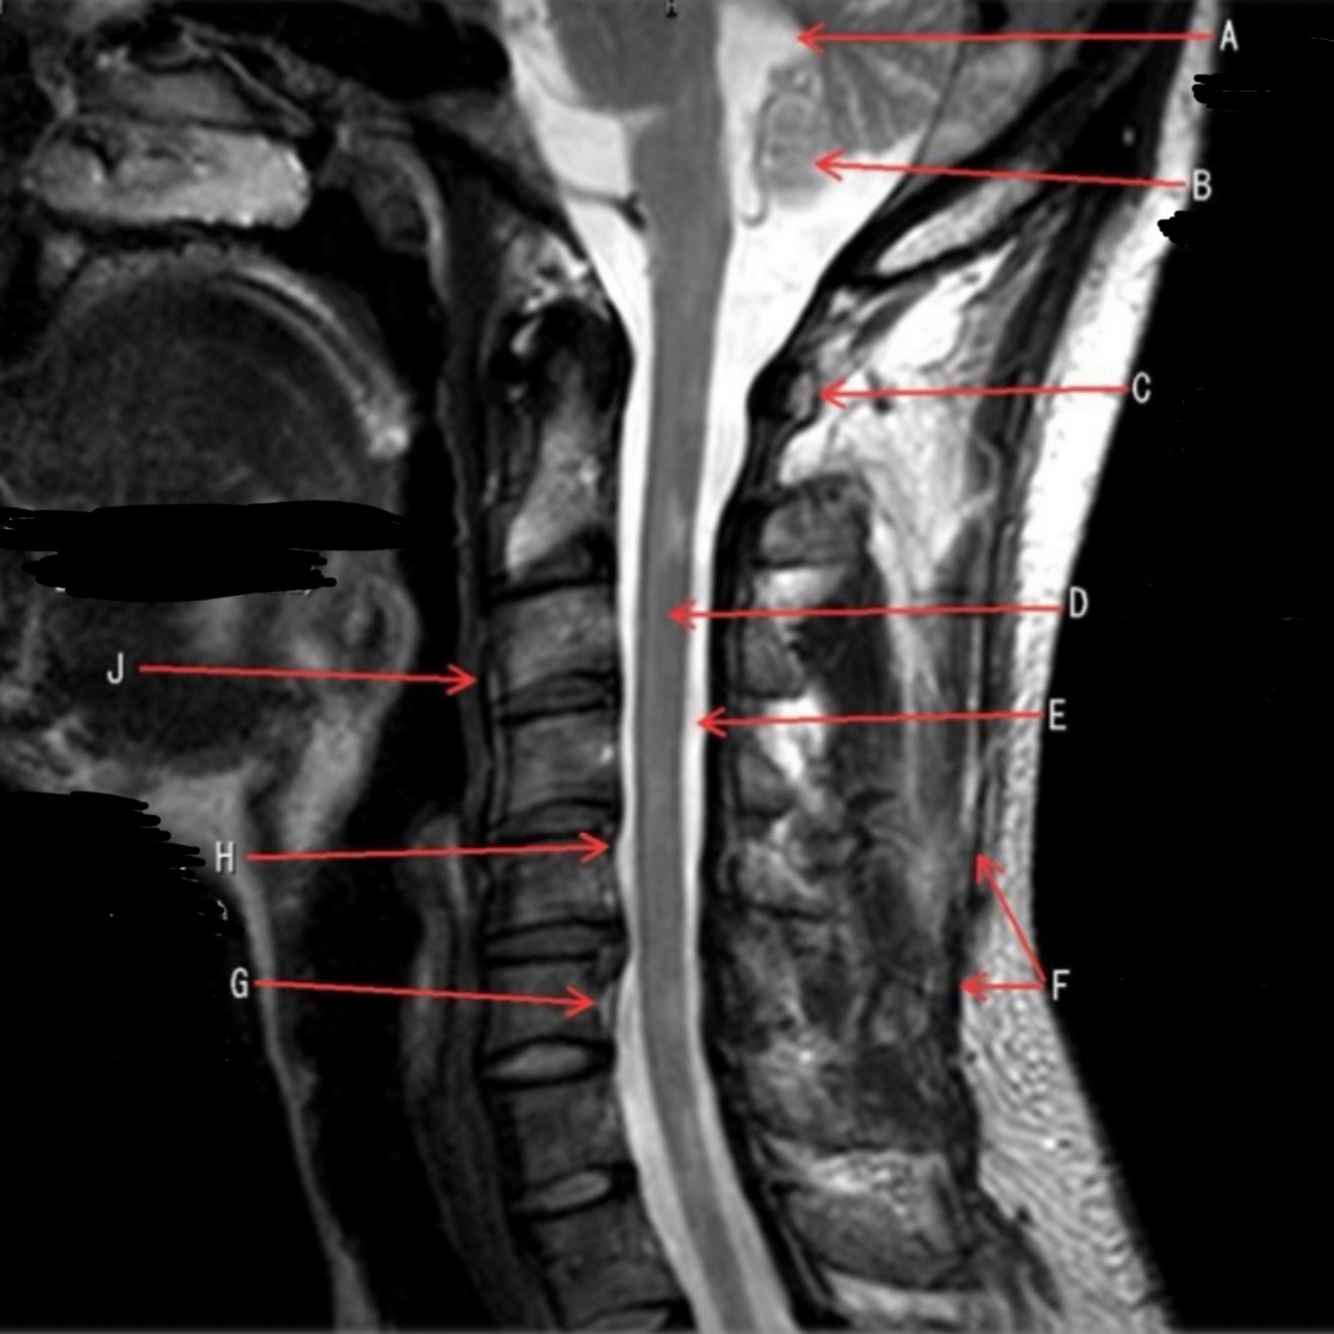

1

Q

What is letter A?

A

4TH VENTRICLE

2

What is letter B?

CEREBELLUM

3

What is letter C?

POSTERIOR ARCH OF C1

How well did you know this?

Not at all

4

5

Perfectly

What is letter D?

SPINAL CORD

What is letter E?

CSF

6

What is letter F?

SPINOUS LIGAMENT

7

What is letter G?

VENUS PLEXUS

8

What is letter H?

POSTERIOR LONGITUDINAL LIGAMENT (PLL)

9

What is letter J?

ANTERIOR LONGITUDINAL LIGAMENT (ALL)